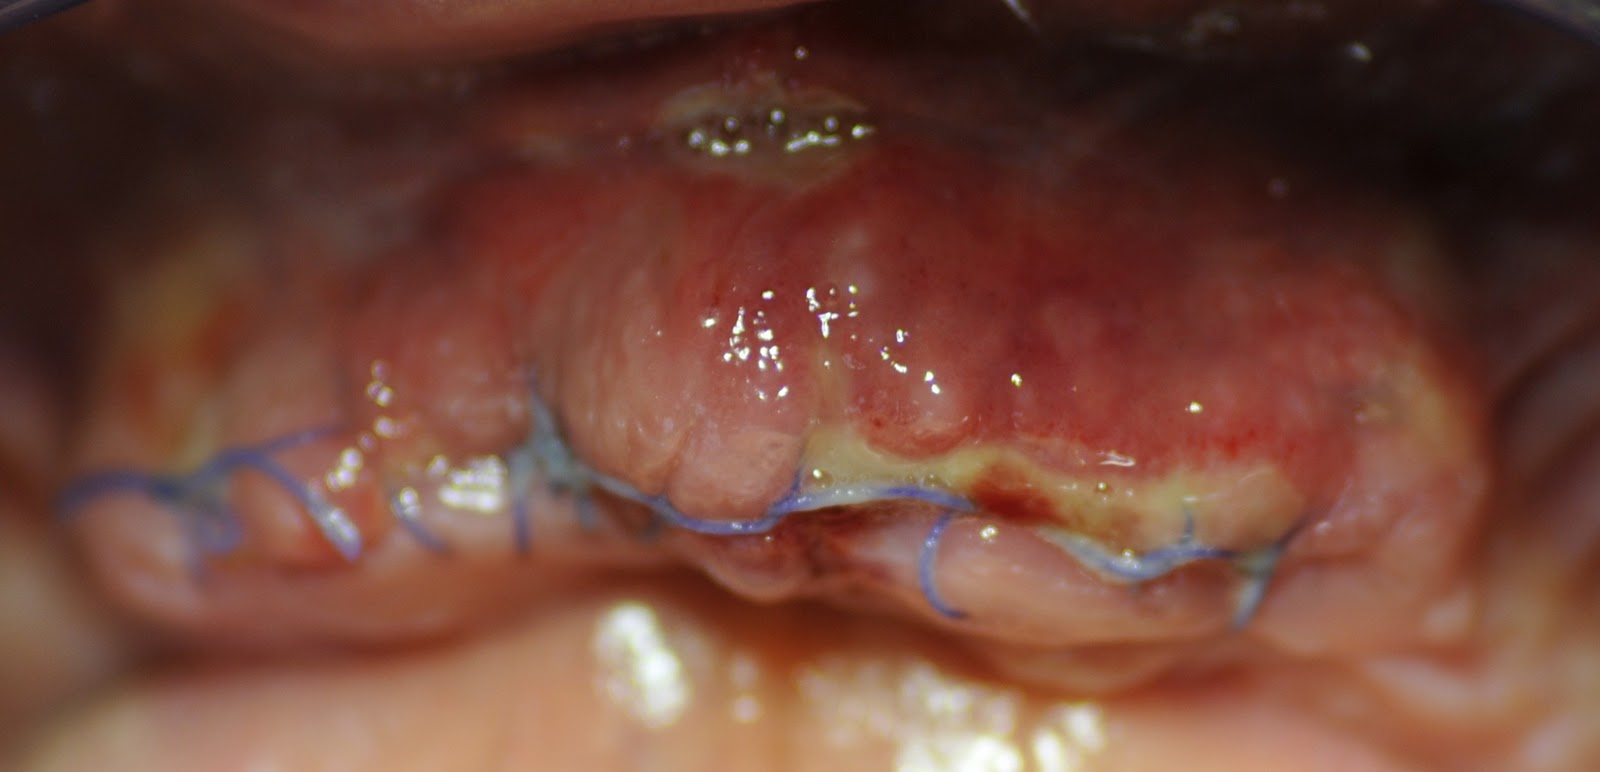

Un Patient non fumeur de 45 ans se présente pour faire vérifier une lésion colorée en regard d'un amalgame sur sa dent 36. Il rapporte que cette coloration a pas toujours était de cette taille et que ça a peut-être évolué. Nous lui préconisons de surveiller et de nous faire part de toute évolution car dans un premier temps nous avons pensé à une coloration de la gencive par tatouage à l'amalgame. Quelques semiane plus tard les inquiétudes ont gandies et nous décidons donc d'effectuer la biopsie exerèse totale de la lésion. La conclusion montre qu'une lésion d'aspect anodin doit toujours être surveiller. (cf http://sitedocteurphilippedubois.blogspot.fr/2013/08/problemes-occlusaux-prothetiques.html ) QPV ?